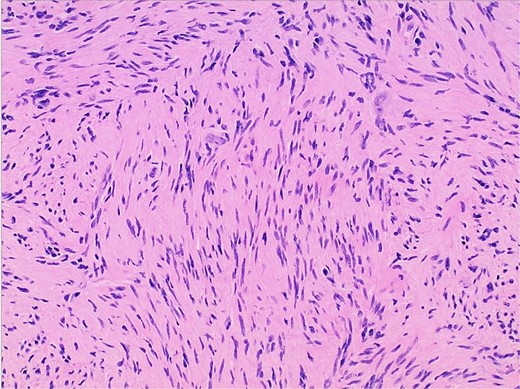

Gross examination and cut sections revealed fragments of tan–white to tan–yellow tissue with some areas of hemorrhage measuring from 1.1 to 3.6 cm in the greatest dimension. Histopathological examination of the excised mass confirmed the diagnosis of a retroperitoneal schwannoma, characterized by S100 positivity (Fig. 3) and degenerative changes, including hemorrhage, hemosiderin, and cystic degeneration (Fig. 4), nuclear atypia (Fig. 5), and perivascular hyalinization (Fig. 6).

Photomicrograph of diagnostic histopathology showing elongated wavy cells with tapered ends of nuclei and modest amount of cytoplasm.